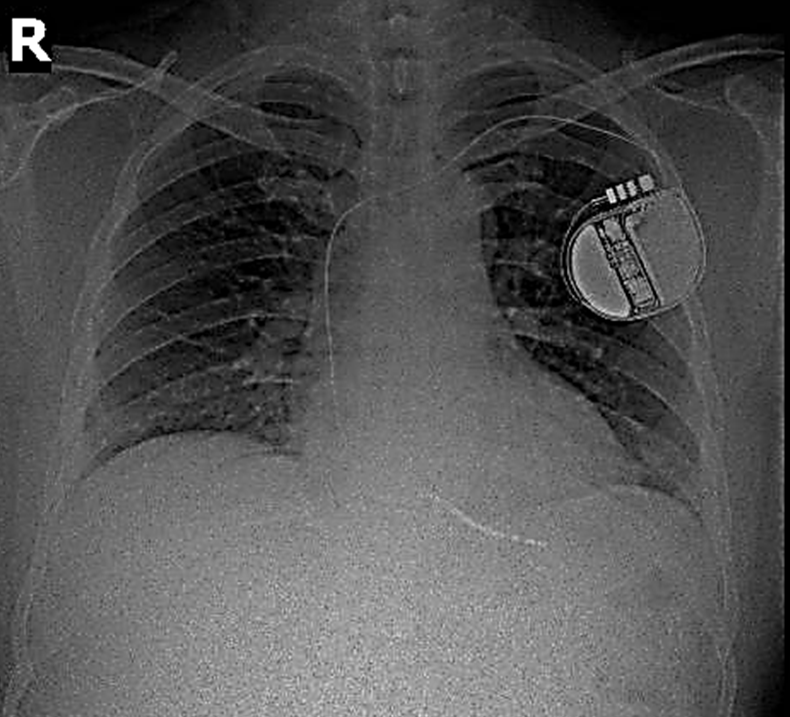

Hình ảnh máy phá rung tim trên phim chụp Xquang. Ảnh BV

Sau đó người bệnh đã được cấy máy khử rung tim (ICD) – một thiết bị nhỏ đặt trong lồng ngực, có nhiệm vụ phát hiện và ngăn chặn kịp thời các cơn rối loạn nhịp tim nguy hiểm bằng xung điện.

Phẫu thuật cấy máy phá rung tim tự động là một trong những kỹ thuật cao, yêu cầu bác sĩ thực hiện phải là người có chuyên môn sâu, giàu kinh nghiệm về tạo nhịp tim. Máy phá rung tim được cấy ghép gồm một dây điện cực kết nối từ máy vào buồng tim phải qua đường tĩnh mạch dưới đòn. Máy sẽ ghi nhận và theo dõi tất cả mọi hoạt động điện học của tim.

Khi tim xuất hiện tình trạng rối loạn nhịp nguy hiểm, tín hiệu bất thường này sẽ chuyển tới máy phá rung, máy sẽ gửi 1 cú sốc điện mạnh để cắt những cơn rối loạn nhịp, đưa trái tim trở về nhịp co bóp bình thường, ngăn ngừa đột tử.